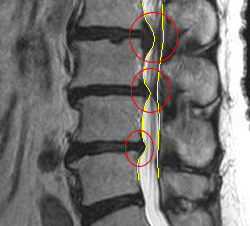

腰の骨のMRI画像を拡大

ヘルニア部位を拡大してみました。

脊髄神経が何カ所も圧迫されているのが、見られます。

レントゲンでは見られなかったのですが、MRIではシュモール結節も見られます。